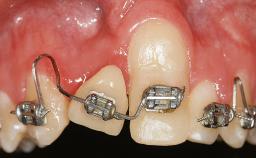

It is sometimes necessary to remove and replace compromised implants. This case is a clear example of the need for multiple steps to achieve an optimal therapeutic result for patients with non-salvageable implants. It illustrates how the lost soft and hard tissues were rebuilt in a sequence that improved the healing of the hard tissues and assured their long-term stability. The 35-year-old healthy patient presented with clinical attachment loss on the proximal and lingual surfaces of the natural dentition. Some gingival recession was present on natural teeth, particularly in the posterior sextants (S1, S3, S4, and S6).